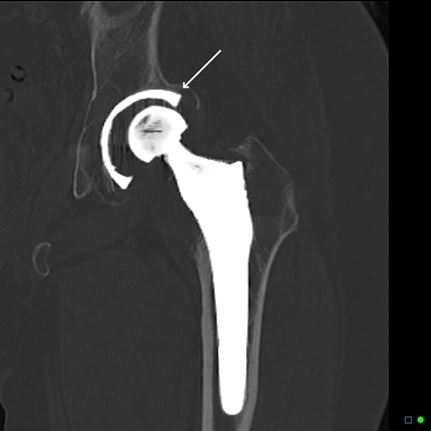

- Расшатывание эндопротеза. По различным причинам может нарушиться связь компонентов имплантата. Это называется асептическое расшатывание. Пациента беспокоит боль в области сустава, а на рентгенограммах мы видим признаки разобщения эндопротеза и кости. В такой ситуации необходимо выполнять ревизионное эндопротезирование.

- Вывихи в искусственном суставе. Случаются ситуации, когда при определенных движениях происходит вывих эндопротеза – разобщение частей искусственного сустава. После вправления однократного вывиха требуется соблюдение ортопедического режима и постоянного наблюдения. А повторяющиеся вывихи эндопротеза являются прямым показанием к выполнению ревизионного эндопротезирования с заменой компонентов и коррекцией их взаимоотношения. Проведение данной процедуры позволит предотвратить дальнейшие вывихи.

- Некорректная исходная установка эндопротеза. Очень редко, но нам приходится встречаться со случаями некорректной установки эндопротеза. Пациента беспокоят частые вывихи, значительная разница длины ног, искривление оси конечности. В таких случаях тоже показано выполнение ревизионного эндопротезирования. Объем операции может варьироваться от замены отдельных компонентов эндопротеза до полного его замещения новым.

- Перелом кости в месте фиксации эндопротеза. Иногда случаются травмы, в результате которых происходит перелом кости в области установленного имплантата. Такая ситуация называется перипротезным переломом, и в некоторых случаях для восстановления целостности кости требуется замена компонентов эндопротеза – ревизионное эндопротезирование.